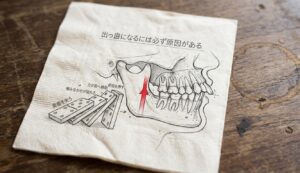

歯の治療で「左右同時」が危険な理由とは?

噛み合わせは椅子の足と同じ構造

つまり、左右の歯を同時に治療してしまうと、噛み合わせの「高さの基準」そのものが失われてしまうのです。